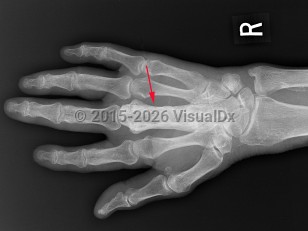

Paget disease of bone

Paget disease is caused by increased bone remodeling and focal bone growth. It is a disease of osteoclasts that is generally seen in older adults and typically affects the skull, spine, pelvis, and long bones of the lower extremities. A common finding associated with aging, Paget disease is identified in 2%-9% of elderly patients, with age of onset at 55 years.

The disease is often asymptomatic but can cause bone pain, fractures, bone deformity, and symptoms due to compression of surrounding structures (eg, hearing loss, lumbar radicular pain). Genetics and viruses are suspected to play a role in causing the disease.